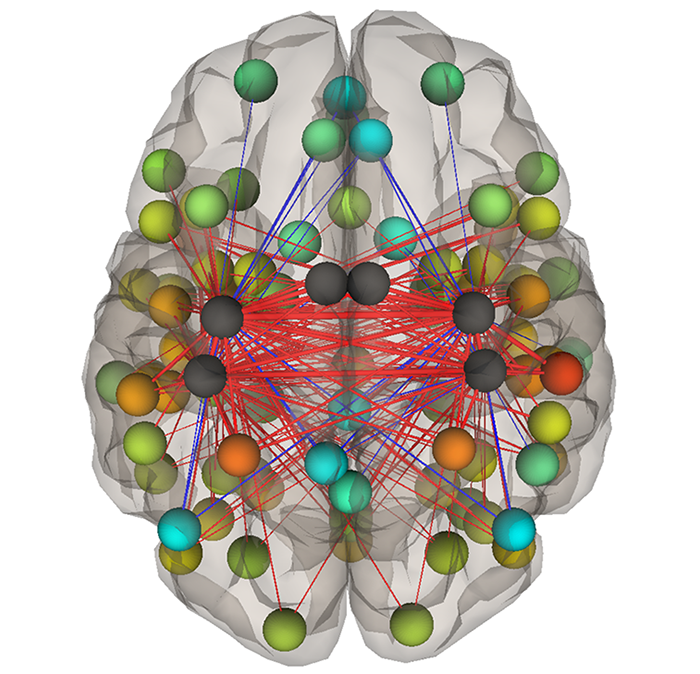

Functional connectivity

One of the main challenges in performing MRIs on children is that they squirm around quite a bit in the scanner (and don’t seem to realize that they are moving). This is also a challenge during task fMRI particularly if the task is a motor task (like squeezing hands or tapping fingers) in a child with hemiparetic cerebral palsy. Task-free resting state fMRI measures changes in blood flow when the children are at rest and allows us to measure how much different areas of the brain “talk” to each other (a measure of functional connectivity) via seeding areas of interest. Using a related technique, we can also investigate how the entire brain communicates as a large neural network (functional connectome).